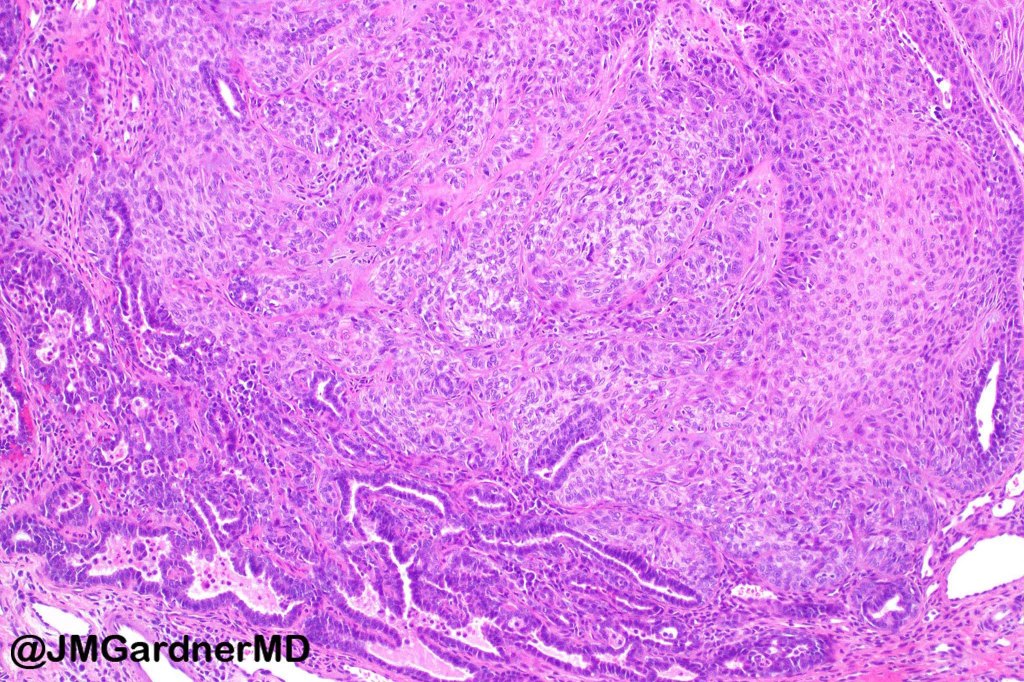

•Scanning magnification shows an exophytic tumor or an epidermal invagination enclosing epithelial covered papillae with a fibrovascular core

•Glands are present at the base of the lesion

•At the edges, the squamous epithelium is in continuity with the glandular one

•The epithelium consists of outer myoepithelial cells supporting an inner layer of columnar cells with abundant eosinophilic cytoplasm showing decapitation secretion

•Dense plasma cell infiltrate

•The base of the lesion may merge with an apocrine tubular adenoma